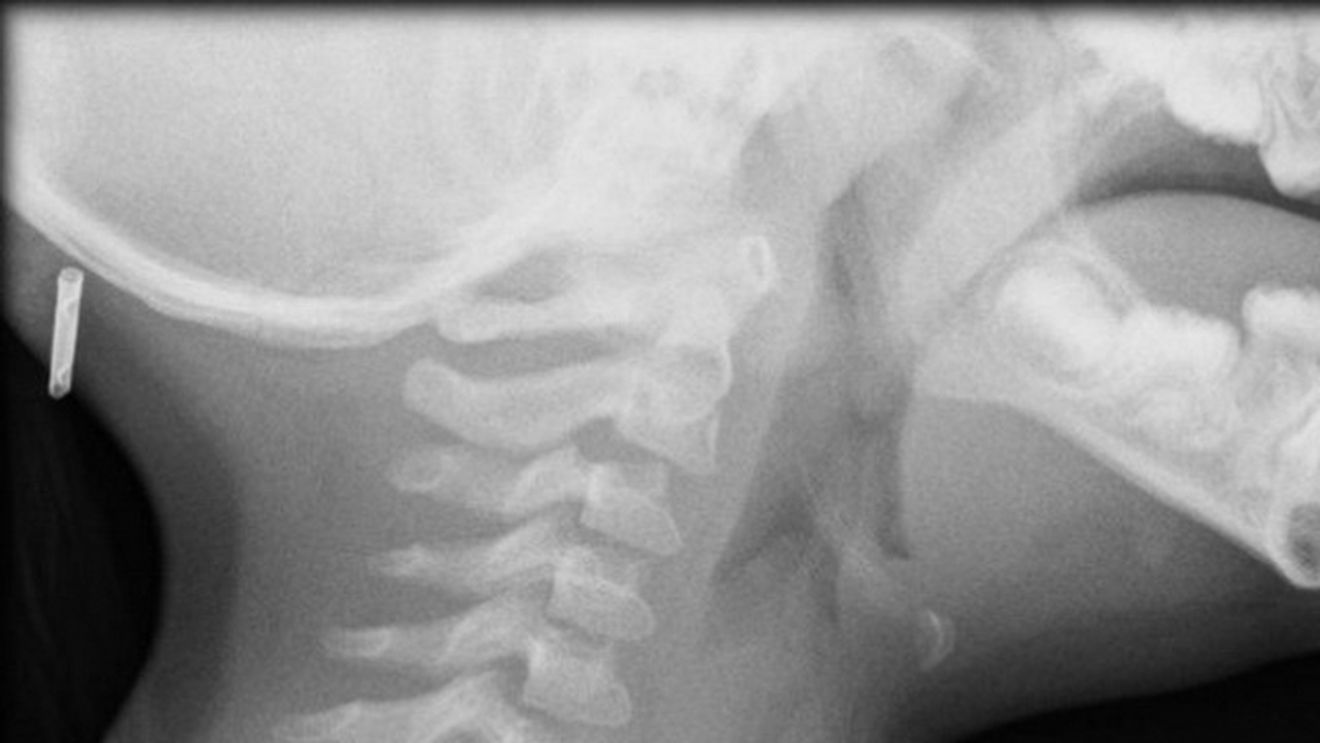

Desi credeau ca tanarul este racit, medicii i-au facut totusi o radiografie.

Atunci au observat ca baiatul avea in gat o lipitoare, scrie Kanal D.

Lipitoarea traia acolo de mai multa vreme, cred doctorii, care in cele din urma au reusit sa indeparteze parazitul.